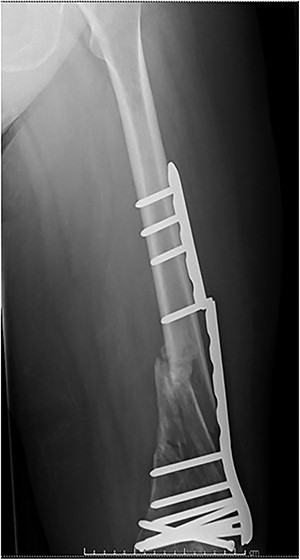

Case 2 (Figs 3–5): here difficulties were clearly encountered in achieving satisfactory reduction in the coronal plane. The screw immediately proximal to the fracture line is too close to the fracture.

Selecting a longer plate would have allowed proximal screws to sit more appropriately in order to reduce the risk of plate fatigue.